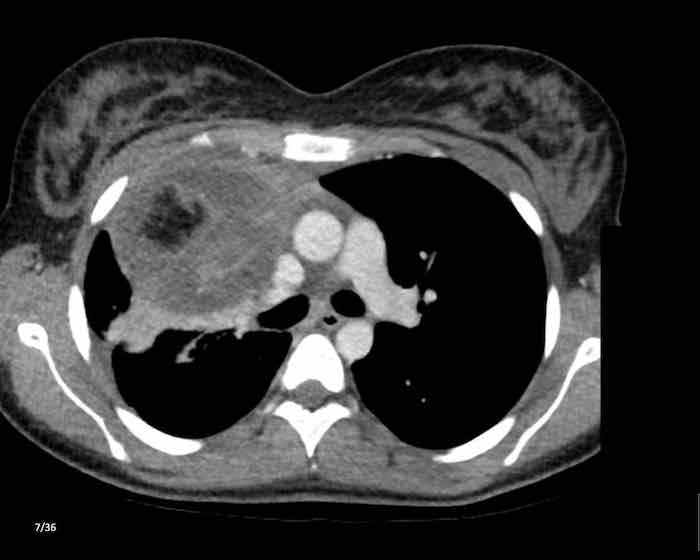

Các hình ảnh này của một nam giới 71 tuổi.

Trên CT ngực, tình cờ phát hiện một khối ở tuyến ức.

Hãy phân tích các hình ảnh. Nhận định của bạn là gì?

Hình ảnh

Một phần tổn thương có ngấm thuốc cản quang và có một số vôi hóa, có thể nằm ở thành nang.

Khi một tổn thương tuyến ức có thành phần đặc, nguyên tắc là… “khi còn nghi ngờ, hãy phẫu thuật cắt bỏ”.

Tổn thương đã được phẫu thuật cắt bỏ dựa trên kết quả CT và kết quả giải phẫu bệnh cho thấy đây là u tuyến ức dạng nang.